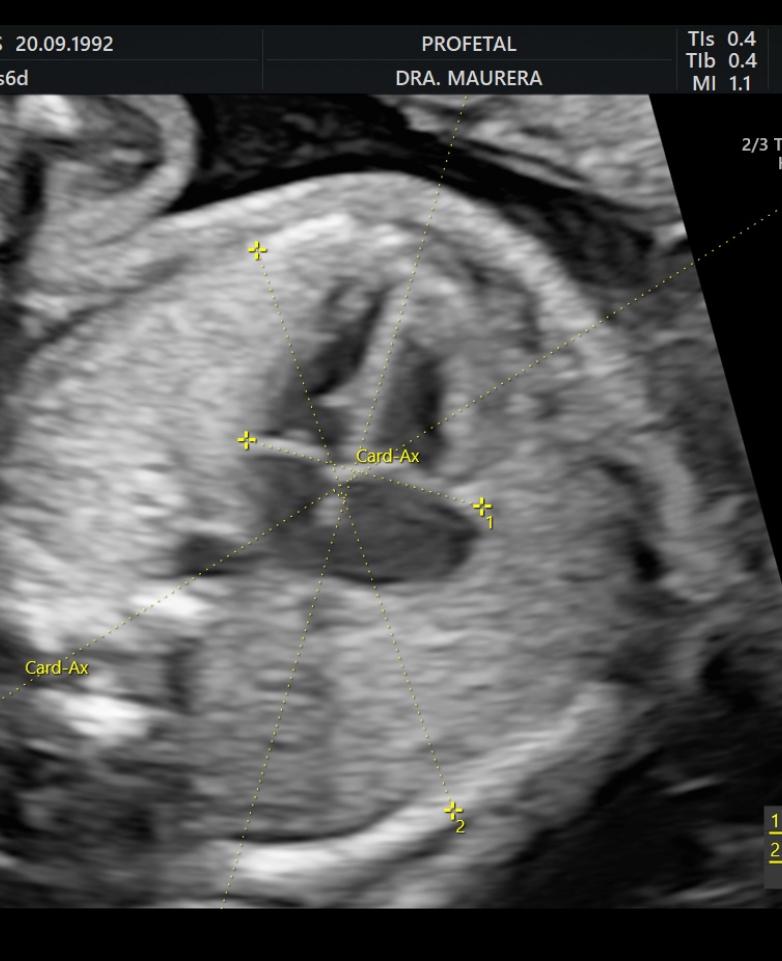

• Ecocardiografía Fetal (Semanas 24-28): Un estudio especializado del corazón fetal para descartar cardiopatías congénitas, especialmente en embarazos de alto riesgo.